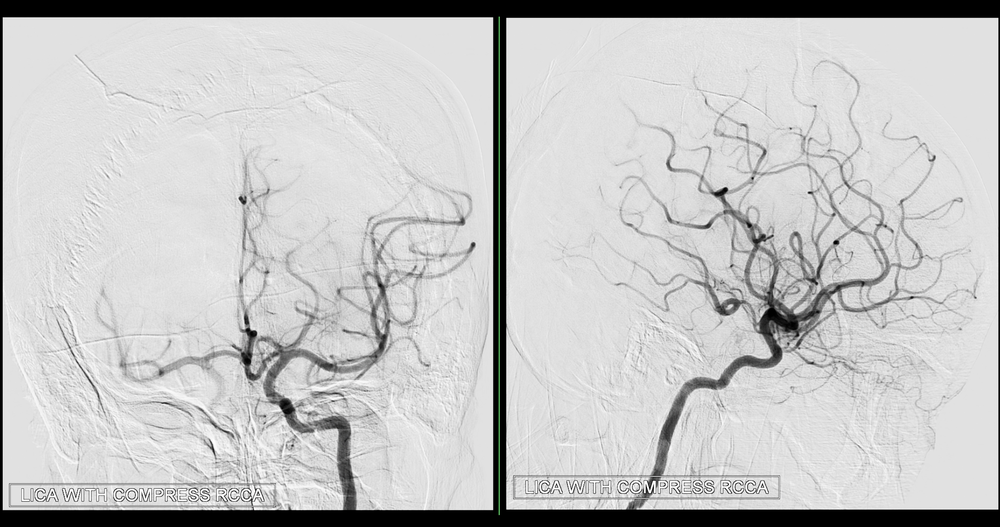

Cas 2 : Pseudo-anévrysme sur branche sous-segmentaire de l’artère pulmonaire droite

après multiples drainages pour infection pleuro-pulmonaire sévère. Contrôle avant et après

embolisation par coil.